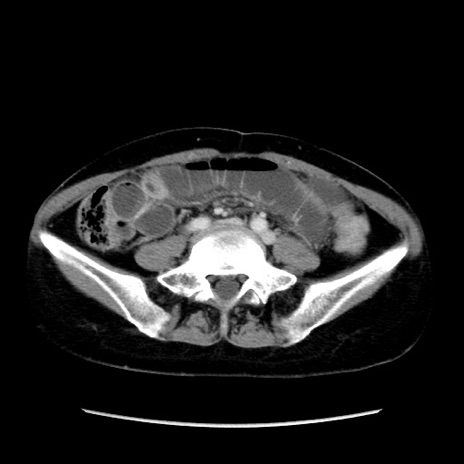

症例32(横断像)

【症例】40歳代 女性

【主訴】上腹部痛、嘔気・嘔吐

【現病歴】約9時間前頃から急に上腹部痛、嘔気、嘔吐が出現。改善しないため救急要請。

【既往歴】子宮頚癌(広汎子宮全摘術、放射線療法)、腸閉塞

【身体所見】腹部:平坦、軟、腸雑音亢進、上腹部を中心に腹部全体に圧痛あり。

【データ】WBC 8400、CRP 0.03